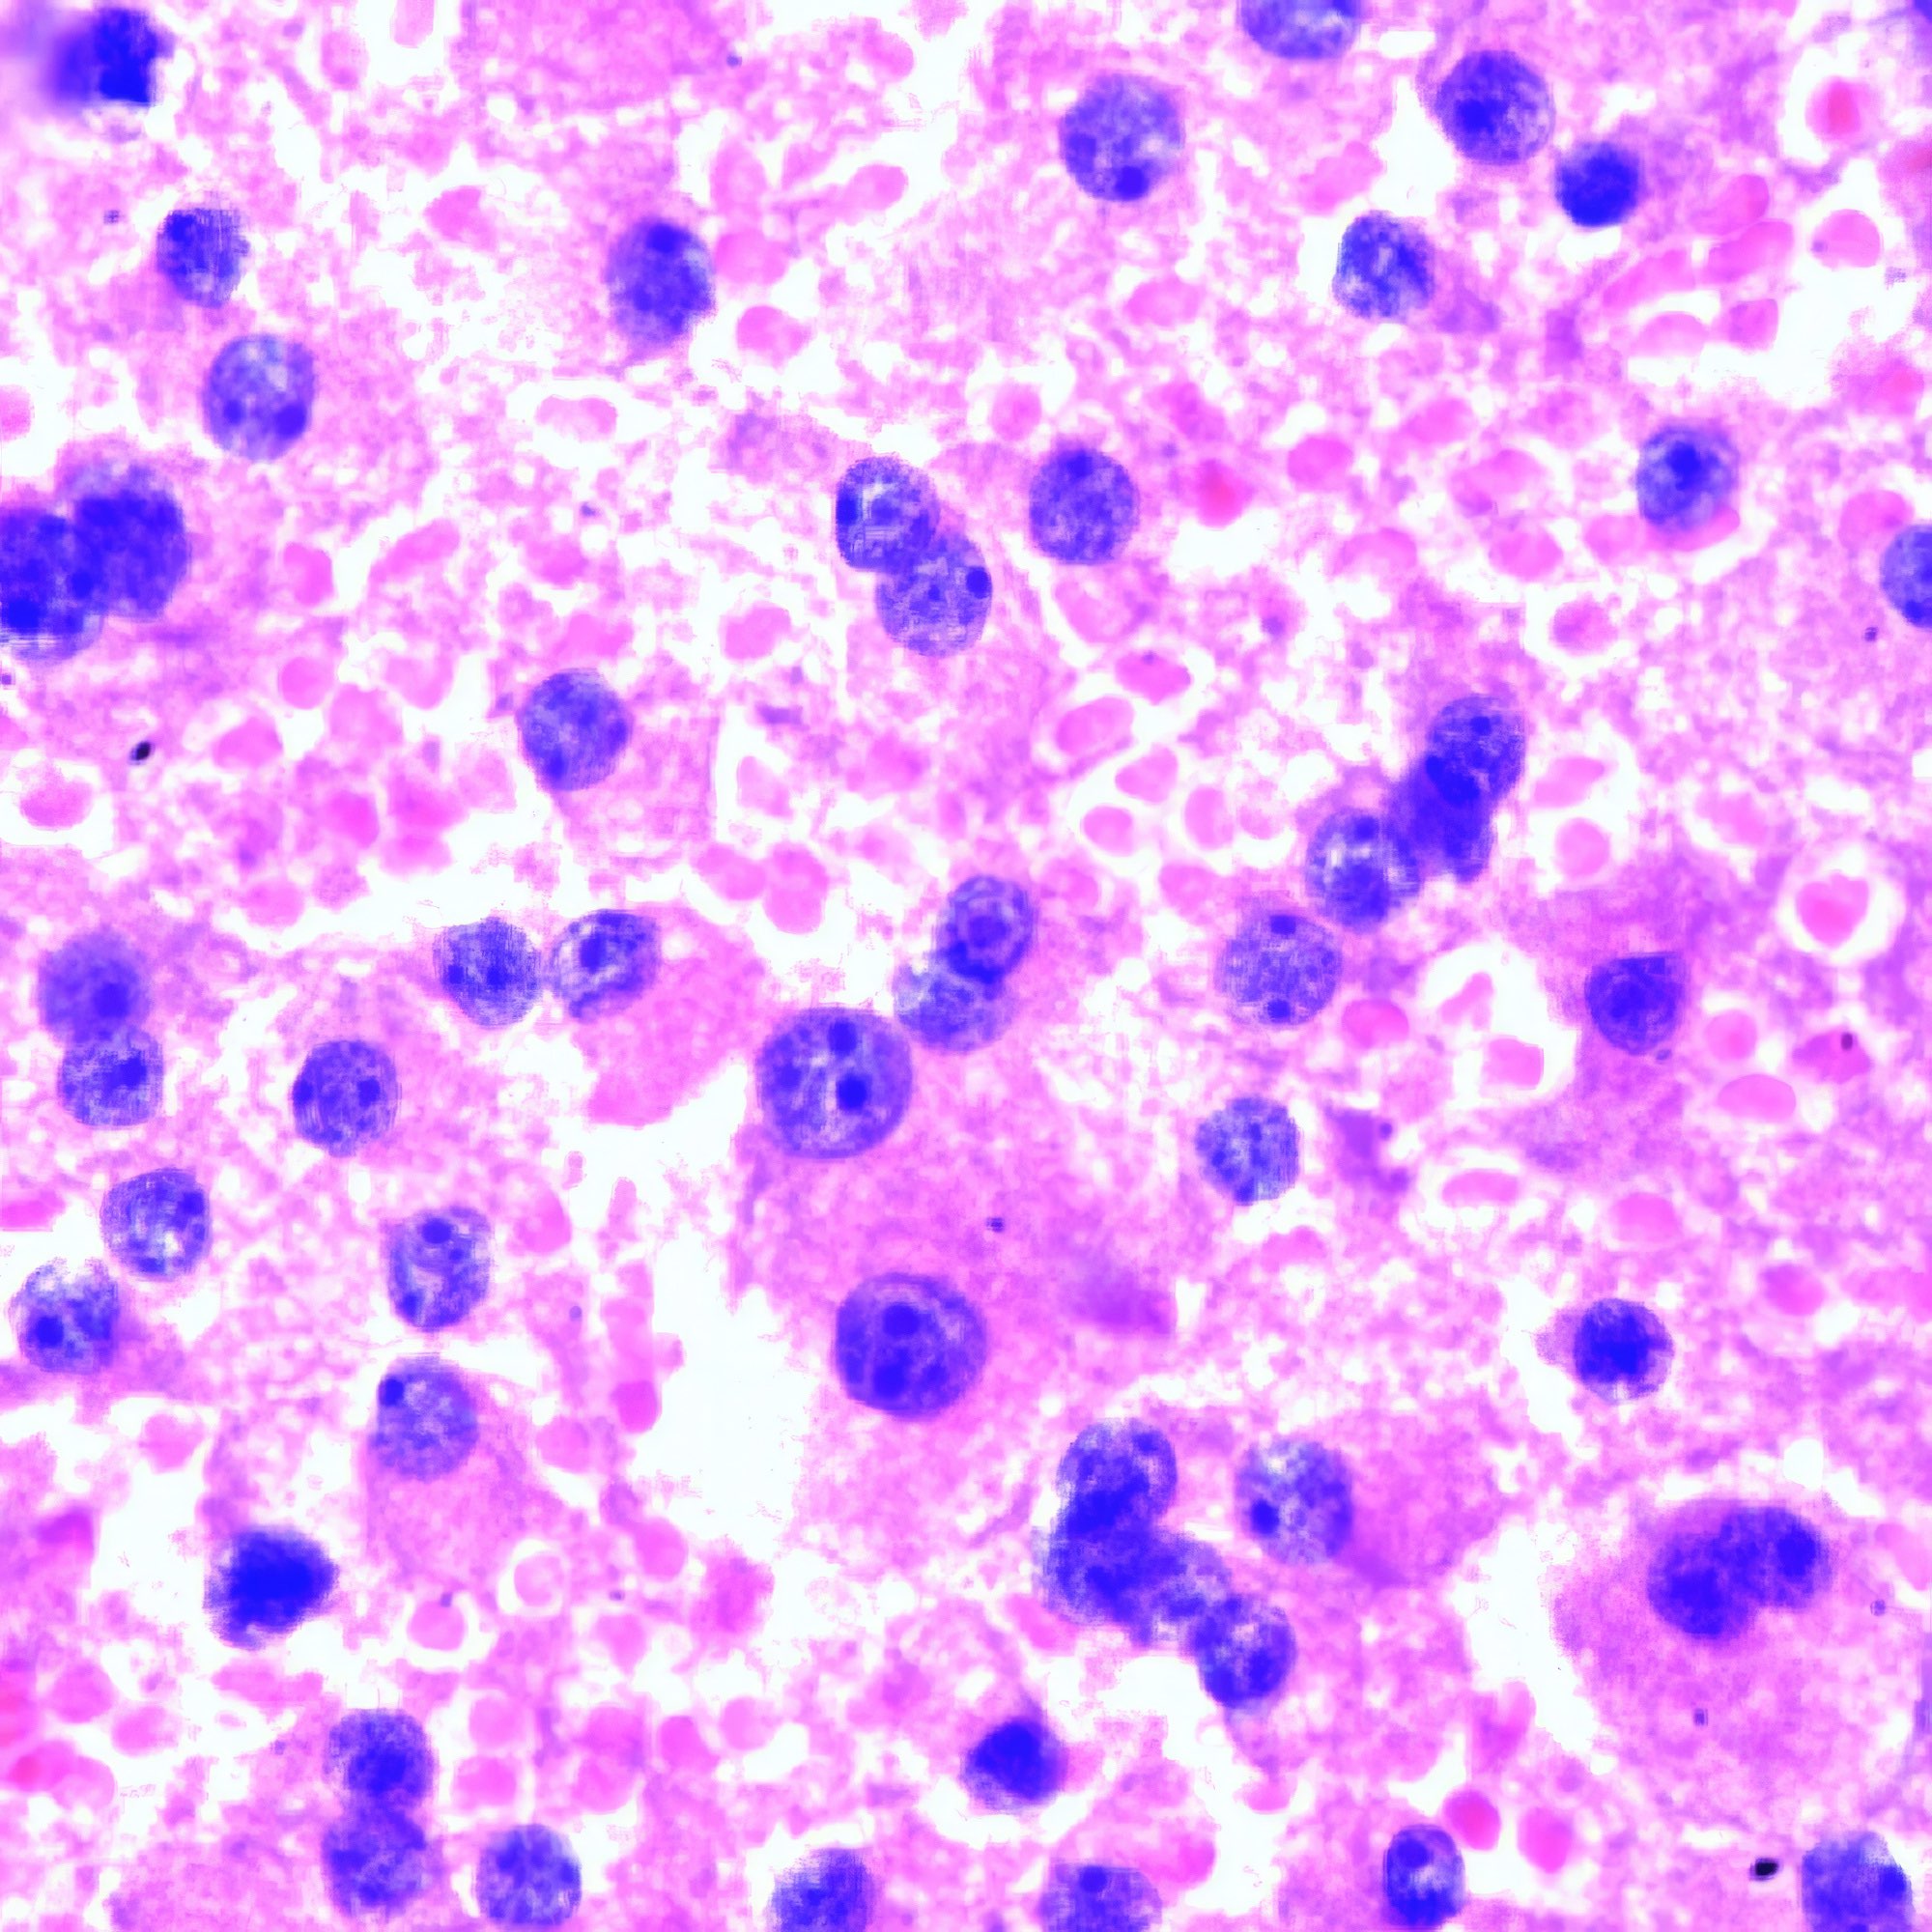

M, 8 Jahre alt, beidseitige Schwellung der Halslymphknoten, weiße Blutzellen 110’000, Lym 43.8%, Gran 23.5%, RBC 2.46, HB 8g/dl, PLT 30 000, CRP 96.

Akute lymphatische Leukämie (ALL)

Die Bilder der Lymphknoten-FNA zeigen außer Blut nur kleine lymphozytäre, keine größeren follikuläre Zellen, wie bei einem Patienten in so jungem Alter zu erwarten. Die kleinen Zellen variieren erheblich in der Form und wenig in der Größe; einzelne von ihnen sind hantelförmig. Vereinzelt geschrumpfte strukturlose pyknotische Kerne (Abb. a li. oben). Die vitalen Zellen zeigen jedoch eine mehr oder weniger normale klumpige Chromatinstruktur (Abb. a, b). Infolge der Trocknung vor der Fixierung erscheinen die Giemsa-gefärbten Zellen im Blutausstrich viel größer, aber auch deutlicher polymorph (Abb. c, d).

Bis vor einigen Jahren wurde die FNA ausschließlich bei erwachsenen Patienten und nur selten bei Kindern angewendet {1}. Im vorliegenden Fall zeigen die ausgezeichneten Bilder, dass das Ergebnis von der Erfahrung des Arztes abhängt, der sie anwendet. Die durch die Pap-Färbung gut sichtbare Chromatinstruktur macht zusätzliche Tests zur Abgrenzung von anderen kleinzelligen Tumoren wie Ewing-Sarkom, Neuroblastom und Wilms-Tumor überflüssig. Die zytologische Diagnose wird durch die klinischen Daten gestützt. Die für die ALL typische Knochenmarksbeteiligung lässt sich an den klinischen Daten ablesen, d.h. an der niedrigen Zahl der roten Blutkörperchen (RBC) und der Blutplättchen sowie dem niedrigen Hämoglobinspiegel (HB). Etwa 80 % der ALL sind vom B-Zell-Typ. Ihre Entwicklung scheint von angeborenen DNA-Veränderungen abzuhängen. Wie in einer neueren Arbeit gezeigt wurde, sind Kinder mit Trisomie 21, der genetischen Ursache des Down-Syndroms, mit einem 20-fach erhöhten Risiko für ALL assoziiert {2}. Im Gegensatz zur ALL tritt die akute myeloische Leukämie (AML) nicht vor der Adoleszenz auf.